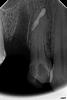

makdoc@bk.ru Опубликовано 16 декабря, 2010 Автор Поделиться Опубликовано 16 декабря, 2010 предположительно-это артефакт от лечения удаленного зуба,который накладывается в проекцию 2.5 зубавот ещё: Ссылка на комментарий

anastasiya.barhatova Опубликовано 16 декабря, 2010 Поделиться Опубликовано 16 декабря, 2010 Мне не нравится пломбировка каналов.И судя по двум другим снимкам - это всё-таки не последствия травмы. Ссылка на комментарий

DokDent Опубликовано 16 декабря, 2010 Поделиться Опубликовано 16 декабря, 2010 Мне не нравится пломбировка каналов.И судя по двум другим снимкам - это всё-таки не последствия травмы.+100!Отдалённый результат-прогноз сомнительный Ссылка на комментарий

Лялька Опубликовано 16 декабря, 2010 Поделиться Опубликовано 16 декабря, 2010 вот ещё: А это не сломанная кюретажная ложка белеет ? Формой напоминает... Хотя-вряд-ли... Ссылка на комментарий

Dr. Surkin Опубликовано 16 декабря, 2010 Поделиться Опубликовано 16 декабря, 2010 скорее всего это остаток пломбировочного материала, вышедшего из 5-го, которого уж нет.На прогноз 4-ки вряд ли влияет. Ссылка на комментарий

Dr.Ru Опубликовано 17 декабря, 2010 Поделиться Опубликовано 17 декабря, 2010 так, терапевты мои взбунтовались и требуют опровержения озвученной мною предыдущей версии по поводу инопланетного вмешательстваони тоже предполагают что это вышедший материал из 5-ки, при чем скорее всего из перфорации Ссылка на комментарий